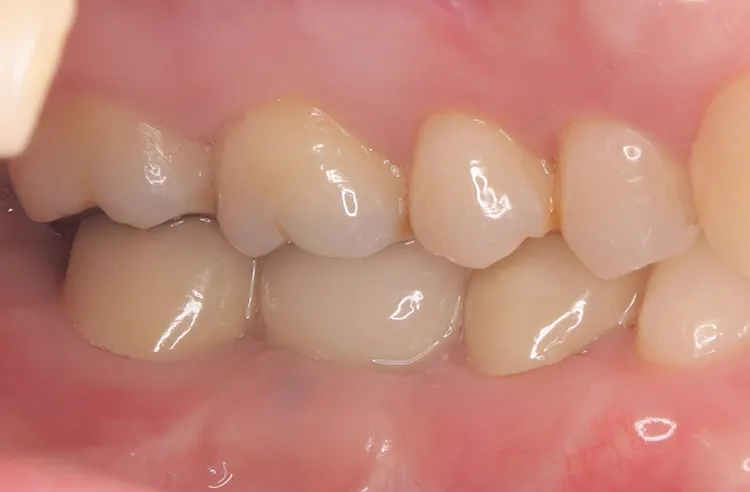

実際にインプラント治療を受けられた患者様の症例をご紹介いたします。

インプラント治療を検討されている方の参考になれば幸いです。

症例1/

症例2/

第一大臼歯1歯欠損をインプラントで回復したケースです。第一大臼歯は永久歯の中で一番最初に生える歯ですが、一番早く傷んでしまう歯でもあります。噛む力の60%を負担し噛み合わせの安定に大きく影響しますので、この歯が欠損すると噛み合わせに悪い影響を与えてしまいます。インプラントで治すことにより噛み合わせが安定するだけでなく、ブリッジのように隣在歯を削らないので天然歯の寿命を延ばすメリットもあります。